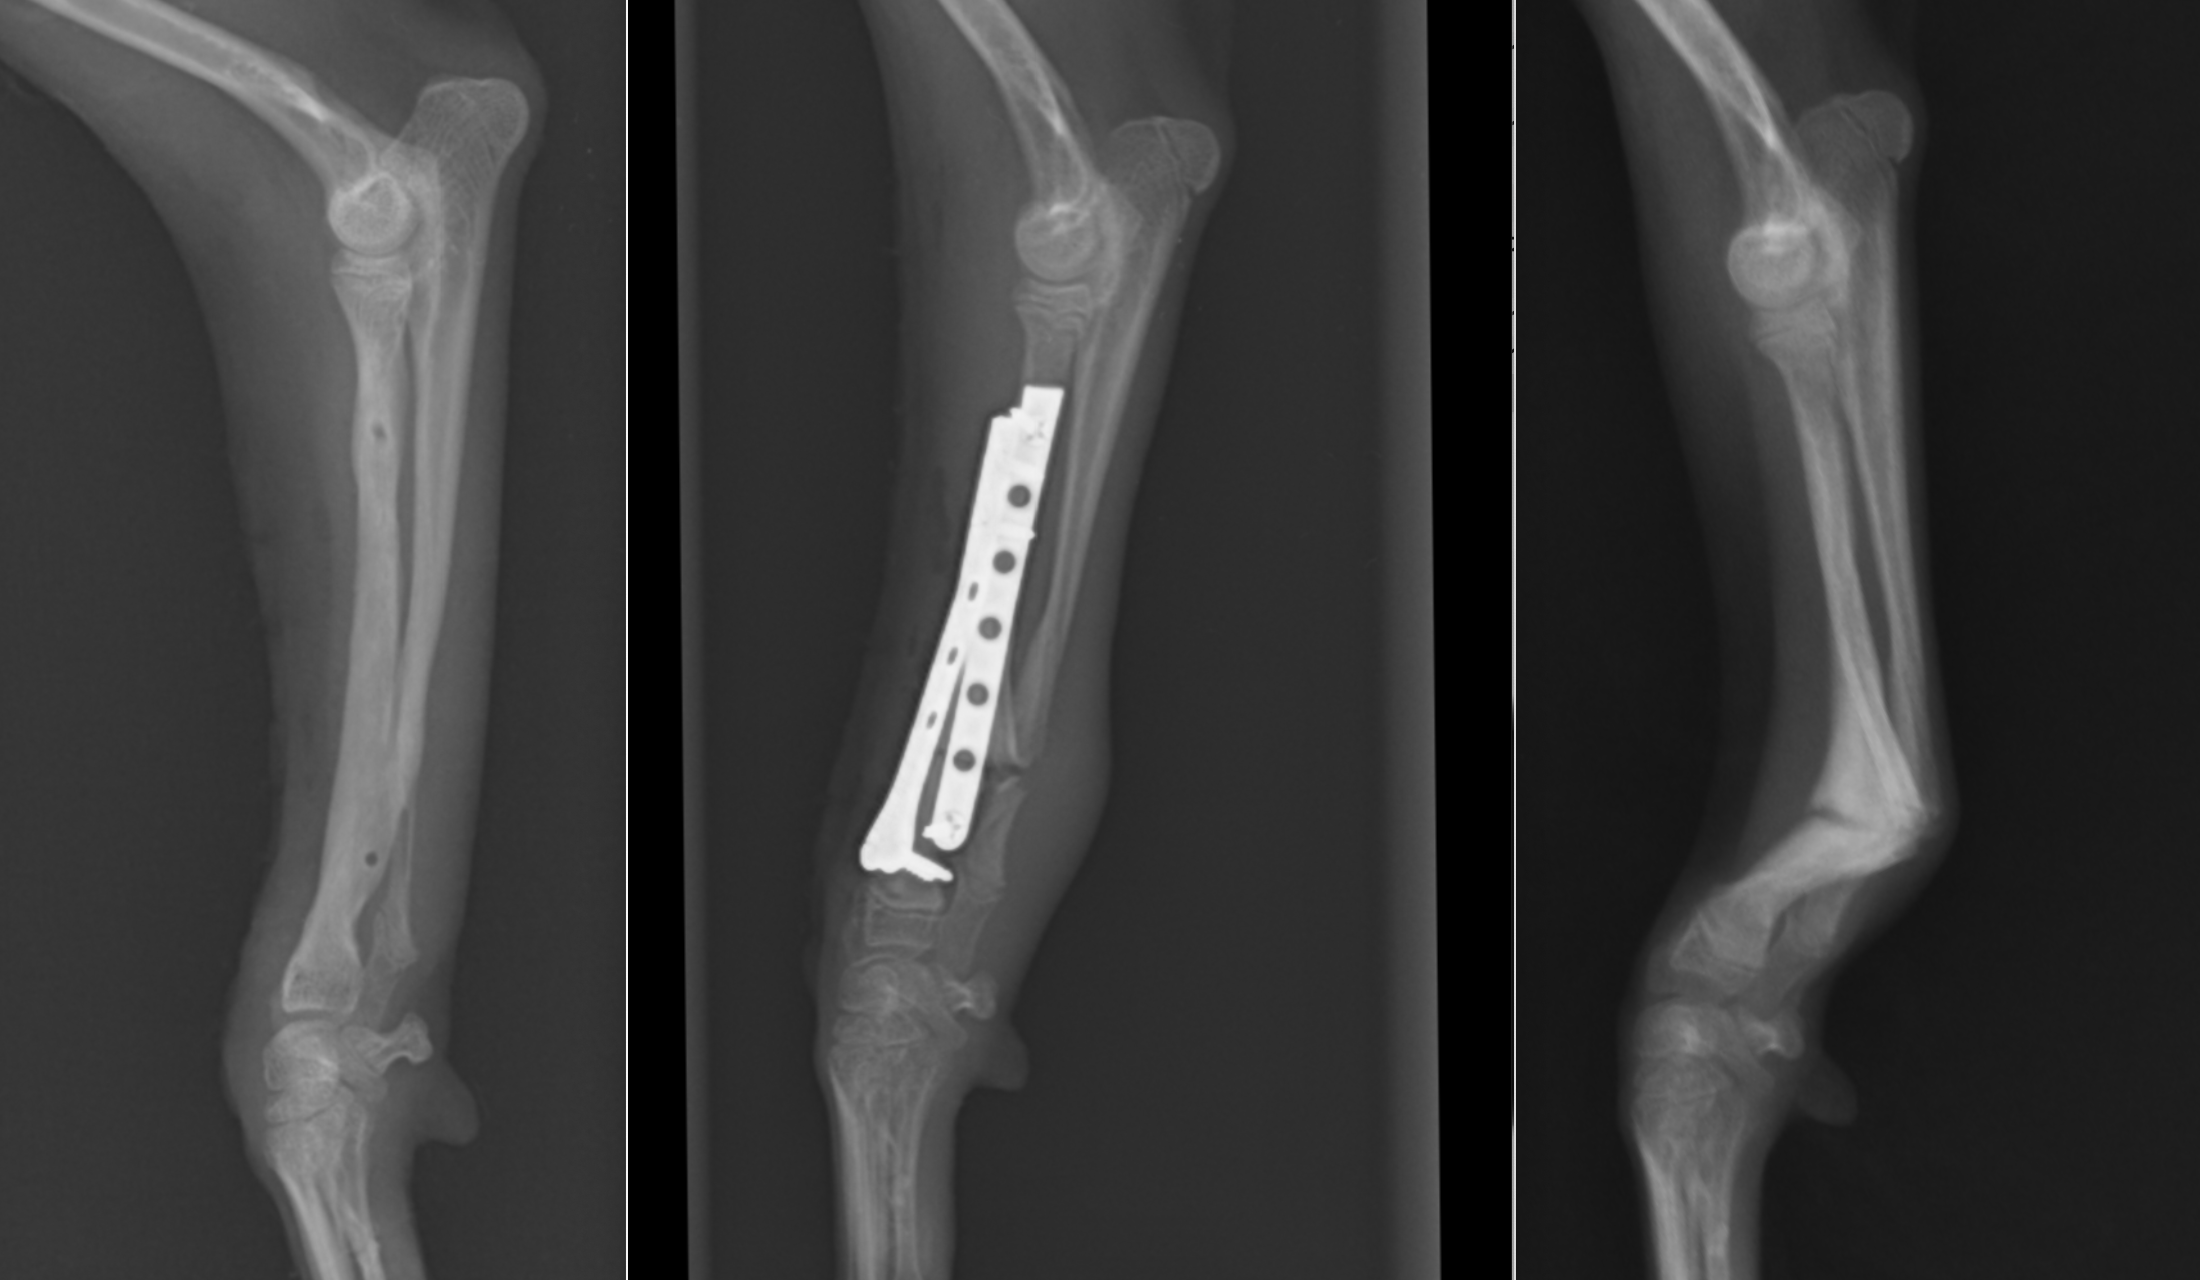

橈尺骨が曲がっているのが分かると思います。この子は、この状態で足を杖のようにしてバランスを取るのに使っていましたが、通常のように負重することはできませんでした。

治療をする場合には細かい計画を立て(角度や長さを術前から計画する)、一度人工的に骨切りを行い、可能な限り真っ直ぐにしてからプレート固定します。一番右が術前、真ん中が術後、左はプレート抜去後になります。